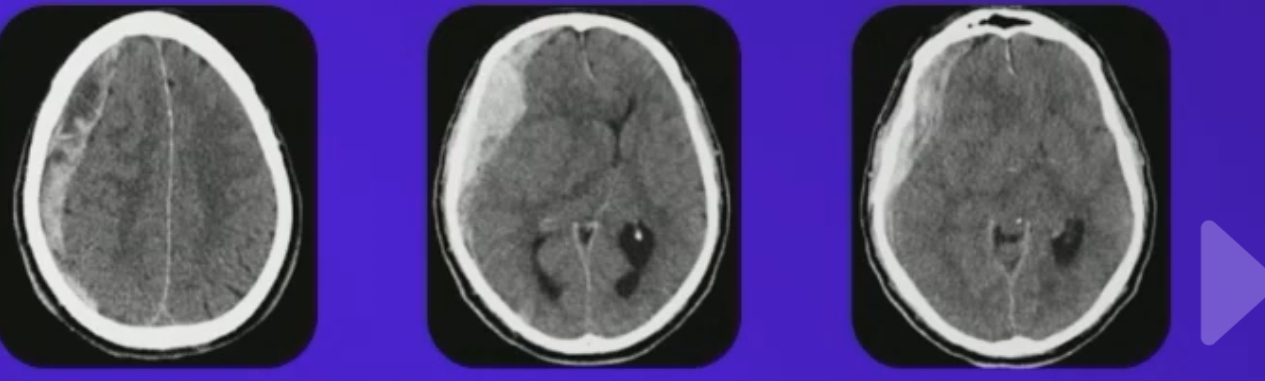

Imagem de edema cerebral e hematoma

Imagem de contusão cerebral, hemorragia subaracnoidea (fisher 4), lesão azonal difusa?

Fisher 4: ventrículos preenchidos